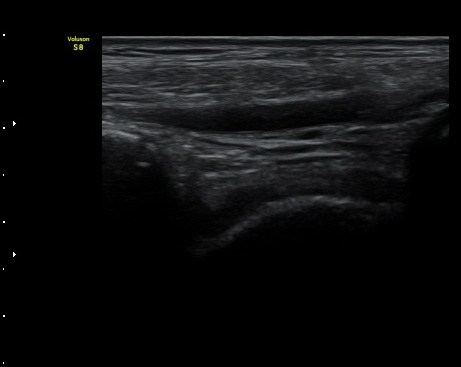

3ÁÖ ÈÄ ÃßÀû°Ë»ç¿¡¼­ ¹Ú¸®µÈ°ñÆíÀÌ °üÂûµÇ°í ÀδëÀÇ Àú¿¡ÄÚ ºÎÁ¾Àº ¾à°£

Áõ°¡µÈ ¼Ò°ßÀ» º¸ÀÓ(±×¸² 3, 4).

ÃÊÀ½ÆÄ°¨½ÃÇÏ °Å°ñºñ°ñÀÎ´ë °ßÀΰ˻翡¼­ °ñÆíÀÇ ¹ú¾îÁüÀÌ °üÂûµÇÁö ¾ÊÀ½(µ¿¿µ»ó 2).